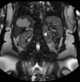

Cystic liver lesion

Choledochal cysts (a.k.a. bile duct cyst) are congenital conditions involving cystic dilatation of bile ducts. [Source: Wikipedia ]